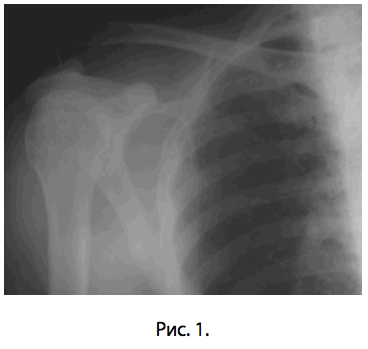

В травматологическое отделение ГКБ им. С.П.Боткина поступил пациент А.А.Ф., 37 лет (и.б. No1068) с травматическим полным вывихом акромиального конца правой ключицы шестидневной давности (рис. 1). Предоперационное обследование заняло двое суток.